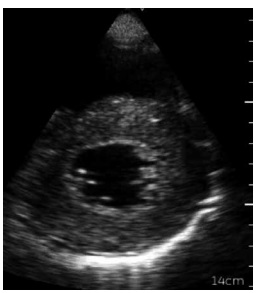

Uma paciente de 55 anos de idade, hipertensa, diabética e tabagista, foi ao pronto-socorro com dispneia, edema de

membros inferiores, estase jugular e estertores bibasais. O quadro iniciou-se junto com disúria, polaciúria e dor lombar, há

três dias. Na admissão: FC de 122 bpm; PA de 83 x 44 mmHg; FR de 24 irpm; sat. a 89 % em ar ambiente; TEC de 4 segundos;

temperatura 38,7 °C; e Giordano positivo à direita.

Considere-se a imagem a seguir.

Assinale a alternativa que apresenta a janela ecocardiográfica à qual a imagem corresponde.